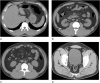

The aim of the study was to determine whether extrapancreatic inflammation on computed tomography (EPIC) is helpful in predicting organ failure in the early phase of acute pancreatitis (AP) as defined by the 2012 revised Atlanta classification.Patients (n = 208) who underwent abdominal computed tomography (CT) within 24 hours after AP onset and admission were retrospectively identified. Each patient's EPIC score, Balthazar score, bedside index of severity in acute pancreatitis (BISAP), and systemic inflammatory response syndrome (SIRS) score were obtained. Primary endpoints were organ failure occurrence and death. Scores were evaluated by receiver operator characteristic (ROC) curve and area under the curve (AUC) analysis.Median age was 45 years (range: 18-83 years). Forty-seven patients (22.6%) developed organ failure, and 5 patients (2.4%) developed infection and underwent surgery. Two patients died. The median EPIC score was 2 (range: 0-7). EPIC score accuracy (AUC = 0.724) in predicting organ failure was similar to that of BISAP (0.773) and SIRS (0.801) scores, whereas Balthazar scoring was not significant (P = .293). An EPIC score of 3 or greater had a sensitivity and specificity of 80.65% and 63.16%, respectively. EPIC scores correlated moderately with organ failure severity (Spearman r = 0.321) and number of failed organs (r = 0.343).The EPIC scoring system can be useful in predicting the occurrence of organ failure, but it does not differentiate severity and number of failed organs in early phase AP.